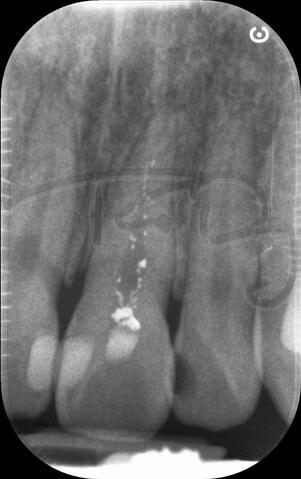

I am pleased to take endodontic referrals. Curved canals >30 degrees and potentially greater than 50 degrees can be negotiated. Sclerosed canals accessed. Post spaces prepared and the patient returned to you ready to restore.In most cases existing crowns, bridges and veneers can be retained with the endodontic access aesthetically restored after the full canal network has been treated.In the first instance I would prefer a radiograph and a brief list of patient expectations and a tooth history.

I really enjoy undertaking root canal treatments - rising to the challenge and helping people out of dental pain for the long term.I was privileged to be asked to speak at the 2016 BDA Conference, where I have a lecture about providing quality endodontic outcomes to patients, working as a generalist. Avoiding problems and pitfalls and maximising efficiency. One of the main matters that he covered was understanding that what is seen on plane radiography is utterly misleading and should not be the criteria by which a generalist continues treatment once it has been started.

At the 2016 BDA Conference, Thomas spoke about providing quality endodontic outcomes to patients, working as a generalist. Avoiding problems and pitfalls and maximising efficiency. One of the main matters that he covered was understanding that what is seen on plane radiography is utterly misleading and should not be the criteria by which a generalist continues treatment once it has been

started.